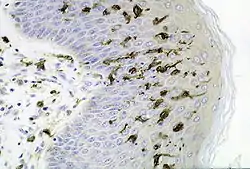

Section of skin showing large numbers of Langerhans cells in the epidermis. (M. ulcerans infection, S100 immunoperoxidase stain.) | |

Langerhans cells (LC) are tissue-resident macrophages of the skin,[2] and contain organelles called Birbeck granules. They are present in all layers of the epidermis and are most prominent in the stratum spinosum.[3] They also occur in the papillary dermis, particularly around blood vessels,[3] as well as in the mucosa of the mouth, foreskin, and vaginal epithelium.[4] They can be found in other tissues, such as lymph nodes, particularly in association with the condition Langerhans cell histiocytosis (LCH).